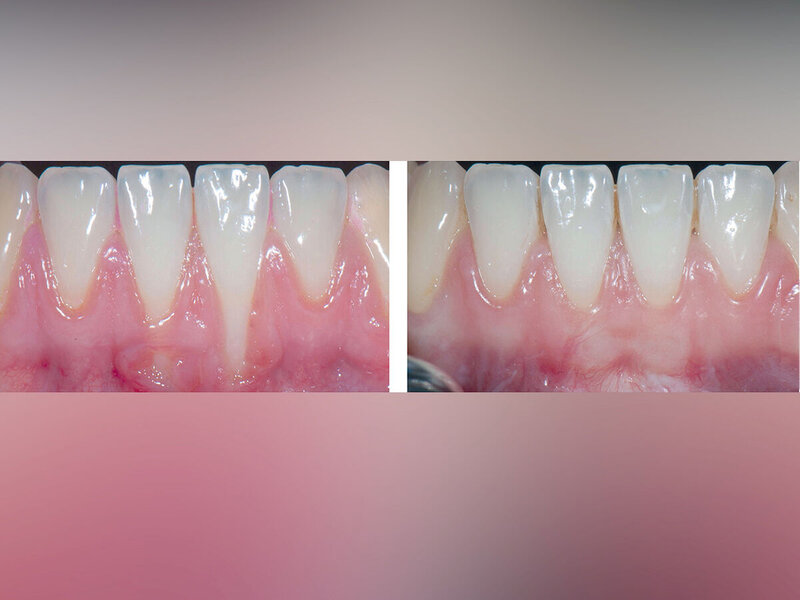

Rezessionsdeckung: Zur chirurgischen Therapie singulärer und multipler Rezessionen ist eine Vielzahl von Techniken entwickelt und in randomisierten Studien (RCTs) untersucht worden. Darauf basierende systematische Übersichten – häufig mit Metaanalysen – sind in den vergangenen 20 Jahren vielfach angefertigt worden, um immer wieder aktuelle Studien berücksichtigen zu können. Dabei konnte überzeugend demonstriert werden, dass mit einigen Techniken vorhersagbar sehr gute Ergebnisse erzielt werden können [Cairo et al., 2014; Graziani et al., 2014; Tonetti & Jepsen, 2014; Chambrone & Tatakis, 2015; Chambrone et al., 2018; 2019]. In den meisten RCTs wurde der Koronale Verschieblappen (KVL) allein oder aber im Vergleich zu KVL plus Bindegewebstransplantat (BGT), ADM, XCM oder Emdogain (EMD) untersucht.

Alle untersuchten chirurgischen Verfahren können bei singulären Rezessionen der Miller-Klassen I und II zu einem signifikanten Rückgang der Rezessionstiefe und einem klinischen Attachmentgewinn führen, ohne dass sich die Sonderungstiefen vergrößern. Dies gilt ebenfalls für multiple Rezessionen, allerdings ist die Datenlage dafür deutlich eingeschränkter.

Techniken, die BGT verwenden (mit KVL oder Tunnel) zeigen im Vergleich die besten Ergebnisse hinsichtlich mittlerer und kompletter Rezessionsdeckung und zugleich einer Verbreiterung des keratinisierten Gewebes.

Bei der Interpretation dieser sehr positiven Ergebnisse ist allerdings zu beachten, dass die allermeisten Studien nur Rezessionen ohne interdentalen Attachmentverlust (Miller-Klassen I und II, Cairo-Klasse RT1) eingeschlossen haben (Abbildungen 3 und 4).